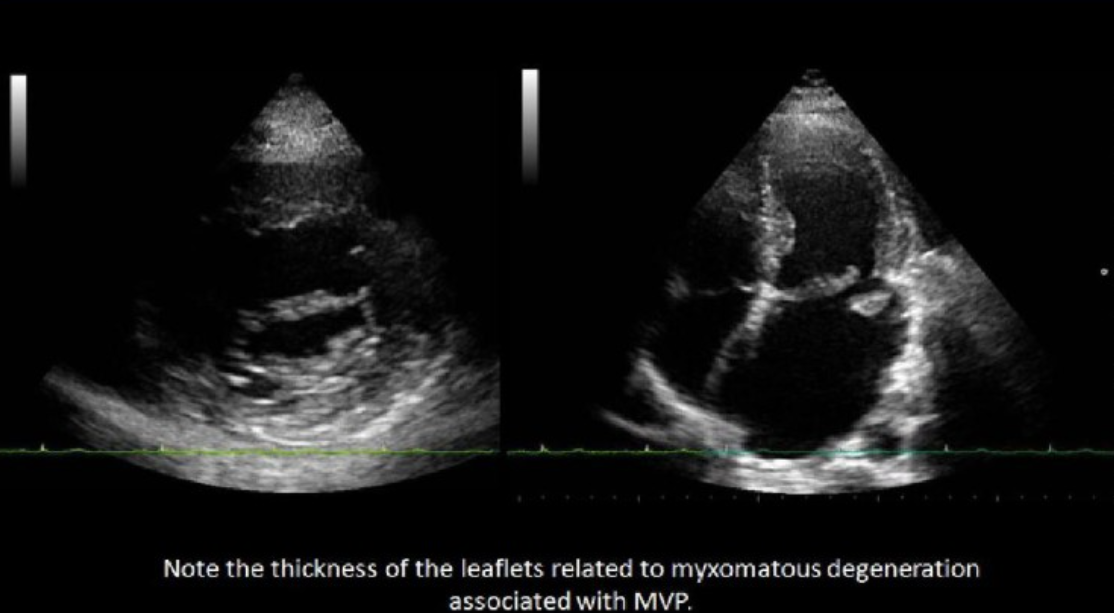

Leaflet redundancy and myxomatous degeneration are common signs of?

MVP